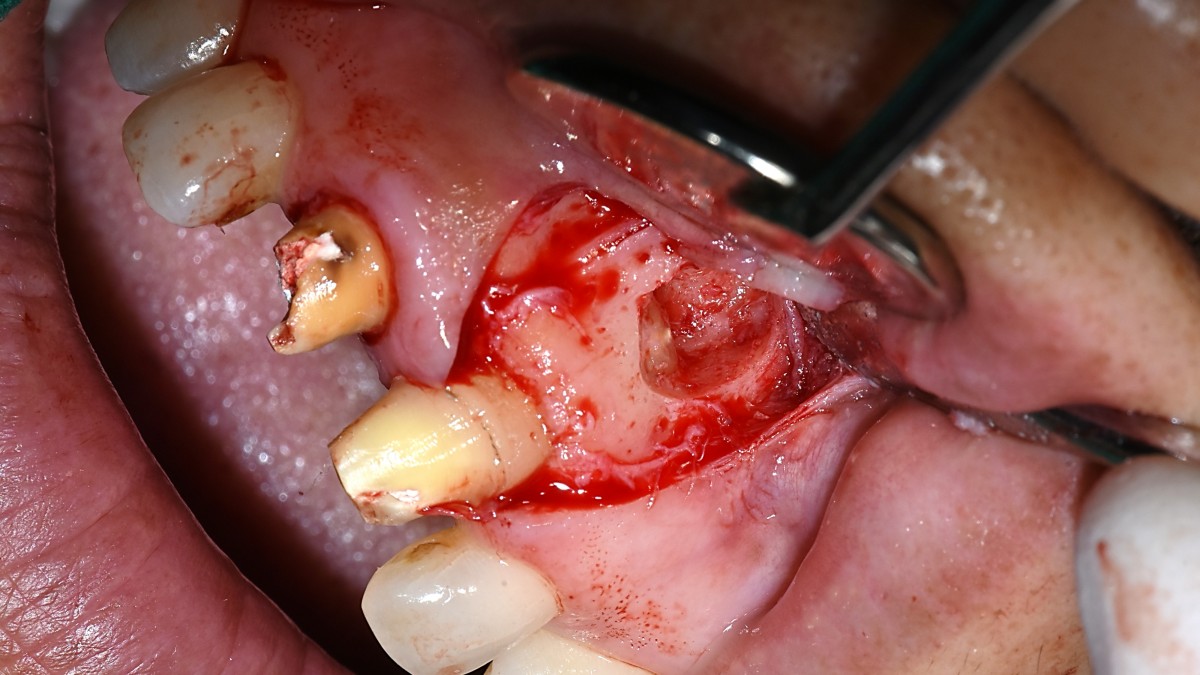

Apicorctomy /central incisor /GBR ; 6-year follow up.

<CJ SBN> Apicorctomy /central incisor /GBR ; 6-year follow up.

▲CBCT. Left central incisor had a apical lesion.